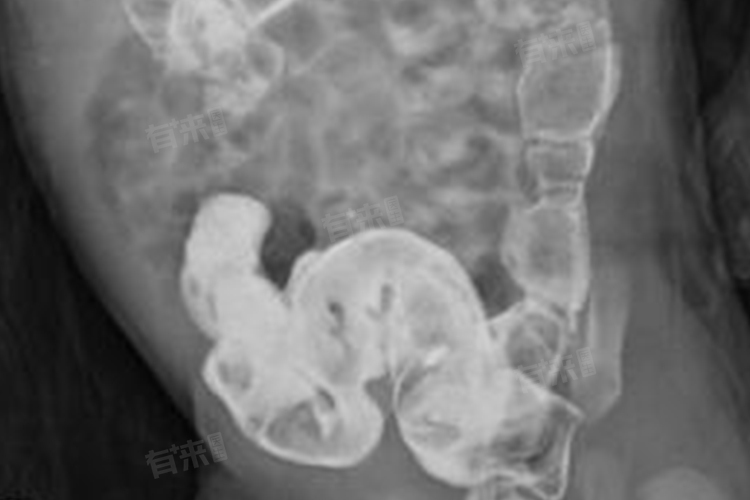

此外,长期患病可导致患儿出现精神萎靡、注意力不集中等精神症状,还可能因反复便秘、肠道感染等出现发热、腹泻等症状。严重者可出现水电解质紊乱和酸碱平衡失调。如果新生儿或婴幼儿出现上述症状,应高度怀疑先天性巨结肠的可能,需及时就医,进行详细的检查,如腹部X线、钡剂灌肠、直肠肛管测压、直肠活检等,以明确诊断,并采取相应的治疗措施。